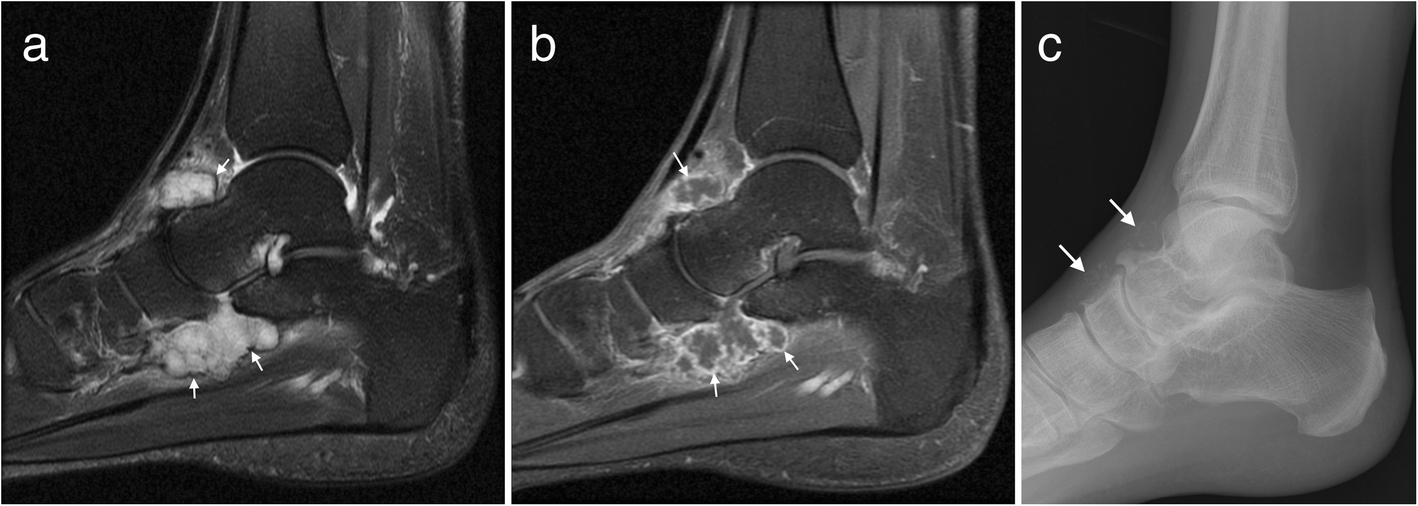

Magnetic resonance imaging is particularly well suited for the medical evaluation of the musculoskeletal (msk) system including the knee, shoulder, ankle, wrist and elbow. This article discusses anatomy, supply and function of the muscles found on the medial plantar aspect/ sole of the foot. The foot and ankle is a complex joint involved in movement and providing stability and balance to the body. Mri anatomy and positioning series module 2: Their main function is contractibility. The foot incorporates countless muscles, bones, tendons and ligaments into simple motion and this chart covers them all. This page provides a gallery of images that presents the anatomical structures found on thigh mri. Synovitis, tenosynovitis, bursitis, and ganglion cysts) > congenital and developmental conditions( eg.dysplasia, tarsal coalition). Mri imaging of the foot • examinations are usually divided into : 3 articles feature images from this case. Parts of the brain & function. Dorsiflexion is when the foot is raised as when you dig in your heels. Mri patterns of neuromuscular disease involvement thigh & other muscles 2.

Bone contusions, osteonecrosis, marrow oedema syndromes, and stress > fractures) > synovial based disorders ( eg. In addition to the three above mentioned muscles there are more structures lying in the medial group of the plantar fascia e.g. Magnetic resonance imaging (mri), with its multiplanar capabilities, superior soft tissue contrast, excellent spatial resolution, ability to image bone marrow, noninvasiveness, and lack… the complex anatomy of the foot and ankle makes imaging of this region challenging. To describe changes in activation of the intrinsic plantar foot muscles after 4 exercises as measured with t2 magnetic resonance imaging (mri). The foot and ankle consists of 26 bones, 33 joints, and many muscles, tendons and ligaments.